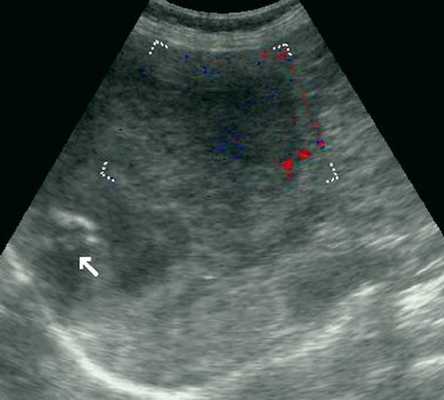

Женщина 50 лет, госпитализирована с болями в верхнем правом квадранте живота. Ультразвуковое исследование органов брюшной полости было проведено в день поступления (рис. 1а, б).

Рис. 1. УЗИ печени.

б) На эхограмме в левой доле печени видно большое гетерогенное образование (5.0x4.0 см), имеющее дольчатое строение.

Диагноз - множественная гемангиома печени

В нашем случае при ультразвуковом исследовании брюшной полости выявлено атипичное строение гемангиомы, динамическая компьютерная томография указывает на типичную гемангиому (рис. 2а, б). При этом важно знать, что только приблизительно в 54% случаев у больных с гемангиомами имеет место характерная перфузия с центростремительным усилением и поздним заполнением [20]. Однако в связи с тем, что этот тип усиления встречается только у 1,6% первичных и вторичных злокачественных опухолей печени, определение структуры данного усиления позволяет уверенно дифференцировать гемангиомы от злокачественных печеночных опухолей [20].